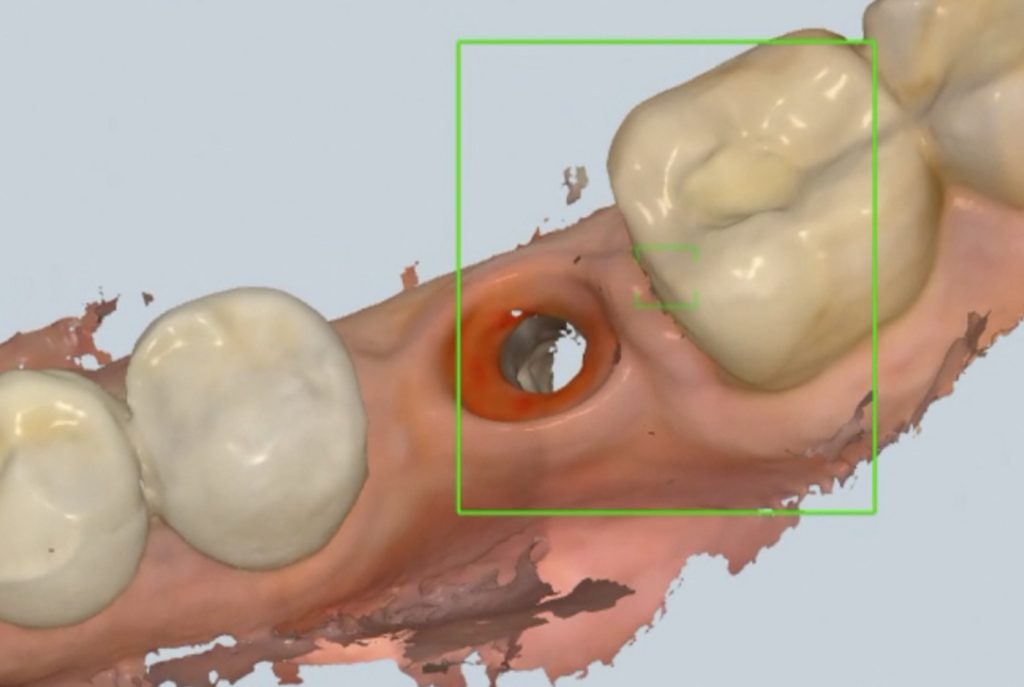

Nếu điều kiện cho phép, bác sĩ sẽ tiến hành lấy dấu hàm bằng vật liệu lấy dấu chuyên dụng (như silicon, cao su) hoặc sử dụng máy scan trong miệng 3D, rồi gửi dữ liệu sang labo. Tại đây, kỹ thuật viên sẽ chế tác hàm răng tạm – thường là hàm nhựa acrylic hoặc composite gia cường – theo thiết kế đã được thống nhất với bác sĩ về khớp cắn, hình thể và thẩm mỹ.